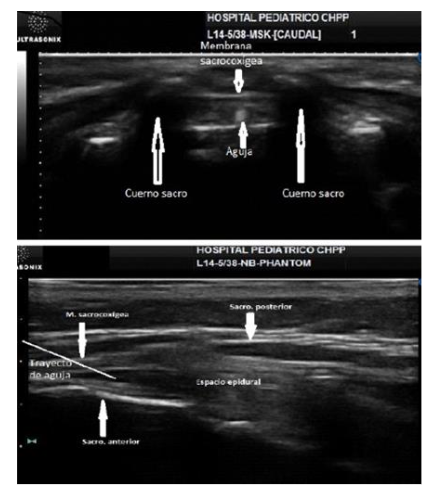

This block is performed under direct ultrasound guidance (Figure 4). The linear transducer is placed in a short-axis view, where the “frog sign” can be seen, with the frog’s eyes being the sacral cornua. Between them, the sacrococcygeal membrane is visible. Anterior to this, the epidural space is visualized, bordered anteriorly by the anterior wall of the spinal canal. The needle can be inserted out of plane with this view, seen as an echogenic dot. When the in-plane technique is performed, once the sacral hiatus is located, the transducer is rotated to the longitudinal axis, where the anterior and posterior walls of the epidural space and the needle entering the space can be seen. 63

Figure 3: Ultrasound-Guided Caudal Block.